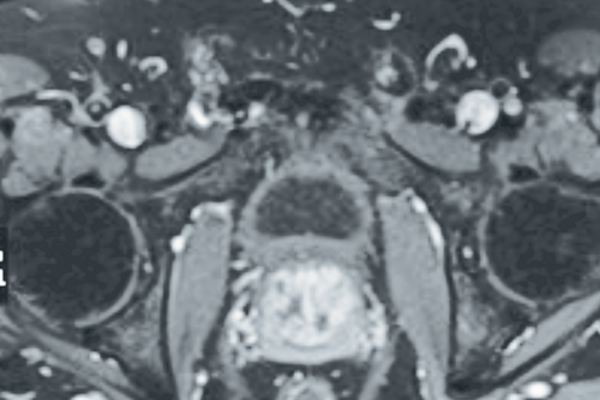

The PROMIS trial – time for multi-parametric MRI before a first prostate biopsy